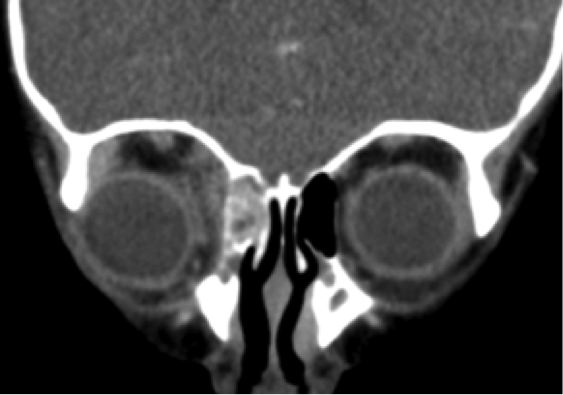

En nuestro caso, al sospechar una celulitis orbitaria, pedimos una TC y una prueba para ver la presión intracraneal (PIC) a Oftalmología.

Aquí se ven unos cortes del TC: